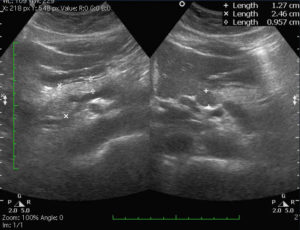

Ткань поджелудочной железы на УЗИ в норме должна иметь одинаковую плотность по всему органу и выглядеть как однородная субстанция.

Если же ее плотность равномерно повышена или понижена, то это указывает на наличие эхопризнаков диффузных изменений поджелудочной железы.

- Повышение эхоплотности. Структура органа становится неоднородной. Наблюдается умеренное увеличение размера органа. Это происходит при остром панкреатите.

- Понижение эхоплотности. При таком эхопризнаке не происходит изменение размера железы.

Подобное состояние свидетельствуют о наличии у больного хронического панкреатита.

- Повышение эхогенности. Означает, что стенки железы замещены жировой тканью, но размеры не отклонены от нормы. Это характерно для липоматоза.

- Гиперэхогенность. Ткани органа сильно уплотнены, размеры могут уменьшаться либо оставаться в пределах нормы. Здоровые клетки замещаются соединительной тканью, что сигнализирует о наличии фиброза.

К таковым стоит отнести случаи нарушения, которые наблюдаются при реакции воспаленной железы. Панкреатит можно подтвердить путем проведения УЗИ.

Также это исследование полезно тем, что с большой долей вероятности позволяет исключить признаки опухолей, новообразований, конкрементов.

Благодаря ультразвуку можно понять, насколько поражена плотность ткани органа, а также увидеть расположение очагов.

Неоднородные диффузные изменения паренхимы печени видны на аппарате УЗИ, исследование является одним из самых востребованных при постановке диагноза.